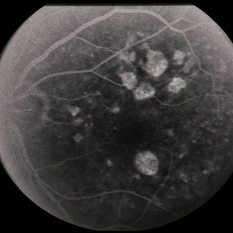

---thumb.jpg/image-square;max$300,300.ImageHandler) Age Related Macular Degeneration

Age Related Macular Degeneration

May 3 2013 by Suber S. Huang, MD, MBA, FASRS

Age related macular degeneration.

Condition/keywords: advanced geographic atrophy, atrophic scar, atrophic spot, geographic atrophy, macula lesion, pigment epithelial atrophy, red-free, window defect